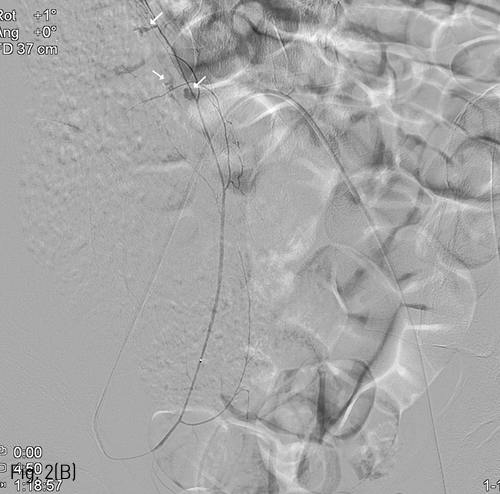

Fig 2B

(B) Multifocal extravasation of contrast media from the small branches on right inferior epigastric angiography could be noted(arrows), and glue embolization was performed.